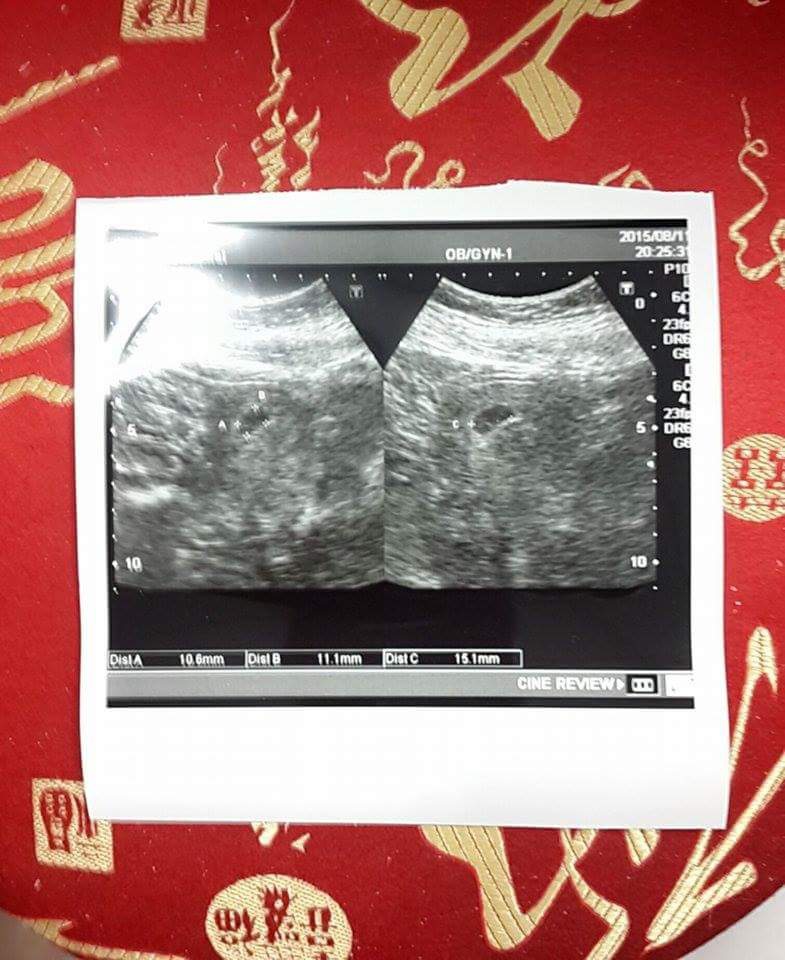

現(2015/9/22)懷孕11週5天,今天安排回婦產科產檢。